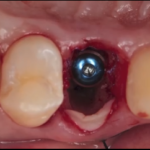

Siti infetti: Impianti postestrattivi e provvisorizzazione immediata

Nella prima parte del presente articolo sono stati analizzati alcuni aspetti riguardanti l'inserimento di un impianto immediatamente dopo l'estrazione di un elemento dentario, con...

Impianti immediati e postestrattivi: evidenze scientifiche e raccomandazioni cliniche